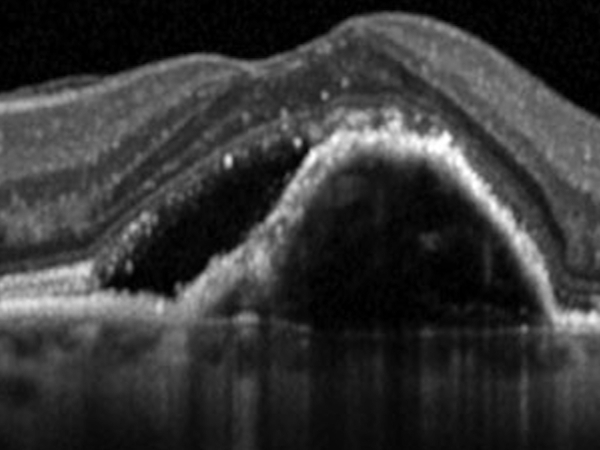

OCT

L’OCT, senza l’utilizzo di mezzi di contrasto, permette, attraverso l’uso di una sonda laser ad infrarossi innocua, di ricostruire l’anatomia della retina nella regione maculare. Un computer trasforma le informazioni ottenute in un’immagine su schermo consentendo una sorta di esame istologico “in vivo” della retina senza effettuare alcun prelievo anatomico sul paziente.